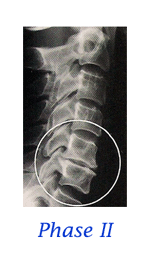

Stages of Spinal Degeneration

When it comes to the spine, the average person’s only interest is with PAIN. Statistics claim that each of us will be disabled with low back pain at least twice in our lives. We may, on average, only miss a couple days work, but many people find back pain to be a lifelong “challenge”. For too long, and too often, the general public has been coerced into thinking that surgery is the only answer for a diagnosis of “slipped disc”. But what is a “slipped disc”? Most people think it is like biting into a tuna sandwich and having all the tuna go out the backside. Oops! That must be really bad! Then again, you may have been told that your diagnosis is a “bulged disc”, “protruding disc”, “herniated disc”, “degenerating disc”, “Fragmenting disc” or maybe “degenerative disc disease”. How confusing can these disc problems be? VERY CONFUSING! . . . continue with Do You Have a "Slipped Disc"?